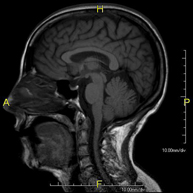

- RM Cerebral (craneal)

Prueba diagnóstica no invasiva que consiste en la obtención de imágenes de alta definición anatómica del cerebro mediante el empleo de un campo electromagnético y ondas de radio (con un emisor y un receptor). No utiliza radiación ionizante. Indicaciones: problemas vasculares, pérdida de memoria, epilepsia, cefalea, malformaciones, sospecha de tumor, meningitis. - RM Cais